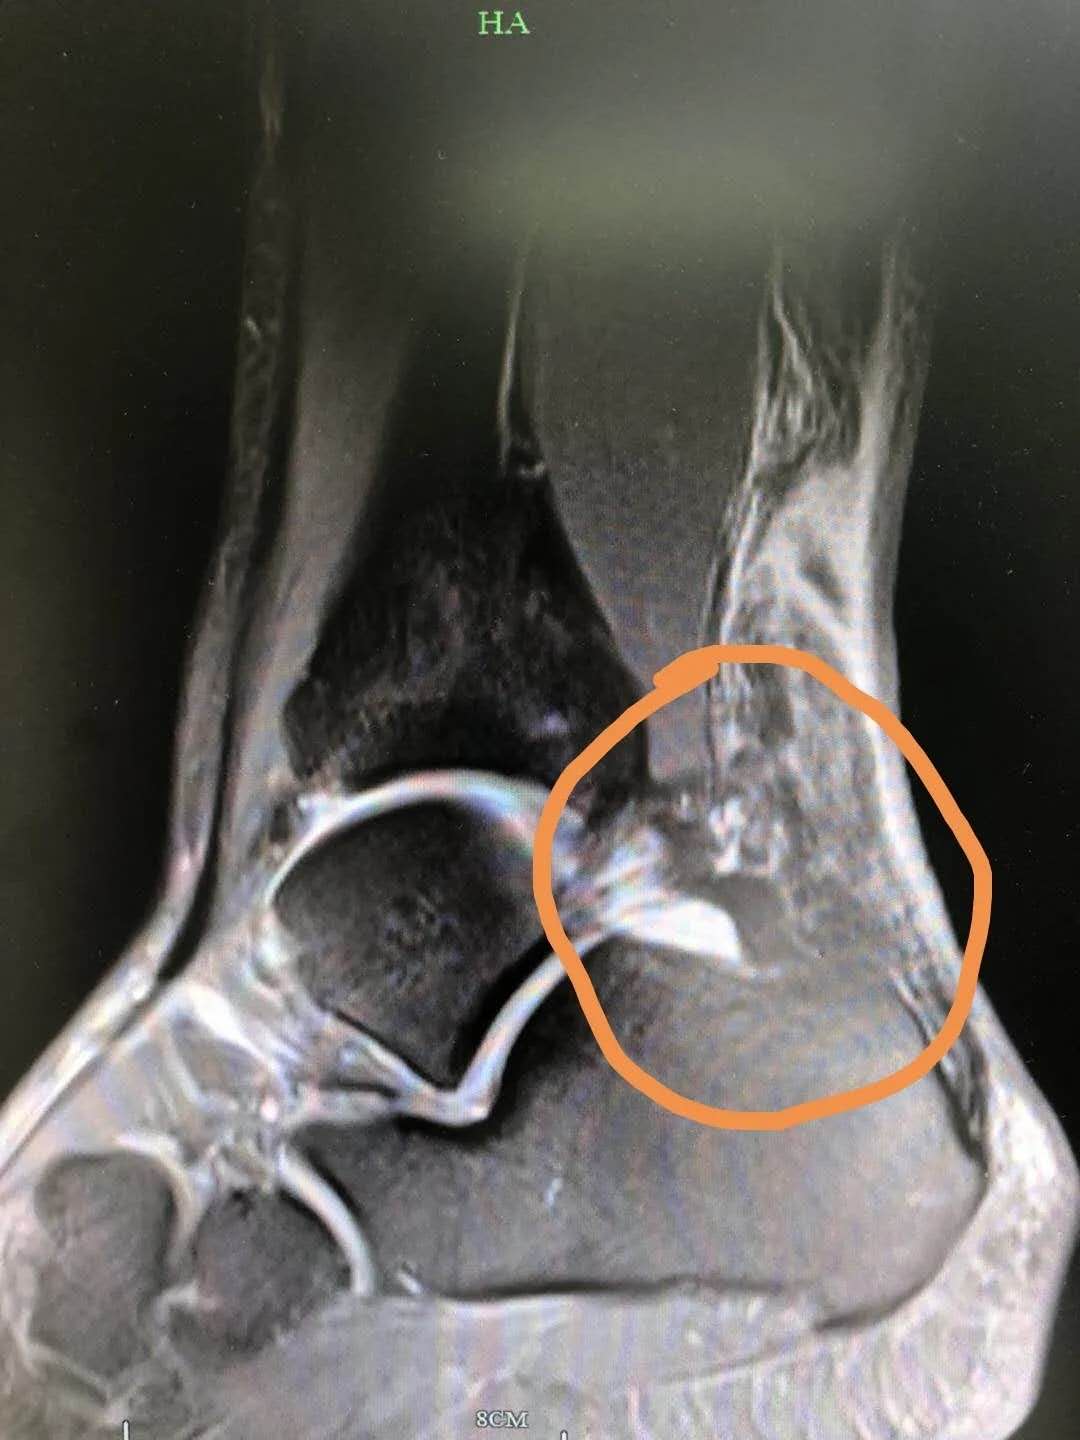

5、受伤后如有上述症状,切记及时就医。临床上常以超声或核磁共振成像来诊断跟腱损伤。